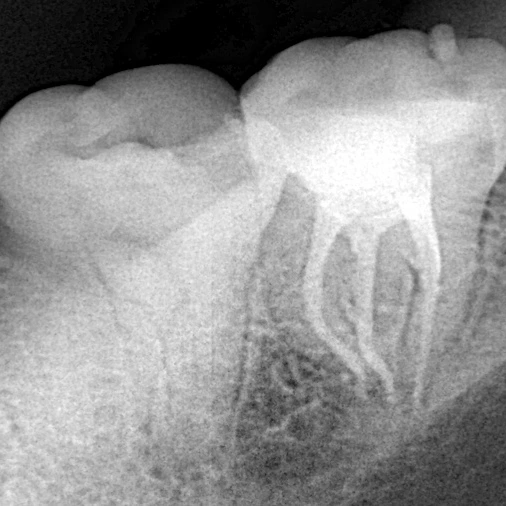

Pre-oprative radiograph showing the slight curve in the apical part of the root

Instrumentation and obturation with One-fil bioceramic sealer